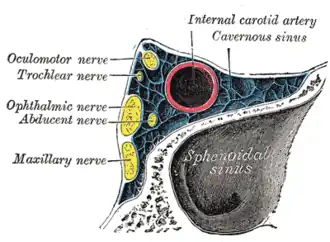

Пещеристый синус занимает особое положение среди прочих синусов твёрдой мозговой оболочки по причине того, что через него проходят следующие важные анатомические структуры:

- глазодвигательный нерв (CN III)

- блоковый нерв (CN IV)

- глазной нерв (первая ветвь тройничного нерва, CN V)

- верхнечелюстной нерв (вторая ветвь тройничного нерва, CN V)

- отводящий нерв (CN VI)

- внутренняя сонная артерия (и сопровождающее её симпатическое сплетение)

Вне зависимости от формы строения синуса черепные нервы с бо́льшим порядковым номером соприкасаются с пазухой на бо́льшем протяжении[1].

Опухоли близлежащих структур (в первую очередь — некоторые опухоли гипофиза) могут приводить к сдавлению пещеристого синуса, что, в свою очередь, будет проявляться признаками нарушения функций тех нервов, которые через него проходят. В частности, у таких больных наблюдаются офтальмоплегия (расстройства движения глазных яблок) и расстройства чувствительности в зонах иннервации глазничного и верхнечелюстного нерва.

Косой разрез через пещеристый синус

Косой разрез через пещеристый синус Вены глазницы (видно впадение вен в пещеристый синус в левой части рисунка)